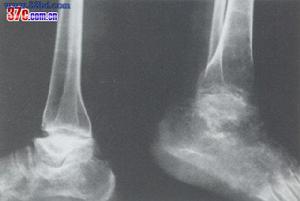

⑷ 骨關節型:見於骺線閉合、骺板軟骨消失之後,包括骨關節面的嚴重破壞、凹凸不平、增生硬化、骨刺形成、骨質碎裂、囊性變、骨端粗大畸形等改變。常累及多關節,X線所見類似退行性(增生性)關節病,是本病的晚期表現。

大骨節病 X線表現臨床上需要與大骨節病鑑別的疾病主要有2類,一類是引起關節粗大、疼痛的疾病;一類是引起軟骨內成骨障礙、短肢畸形、身材矮小的疾病。鑑別時主要應掌握各自疾病的特徵,以及大骨節病有地區性等特點。